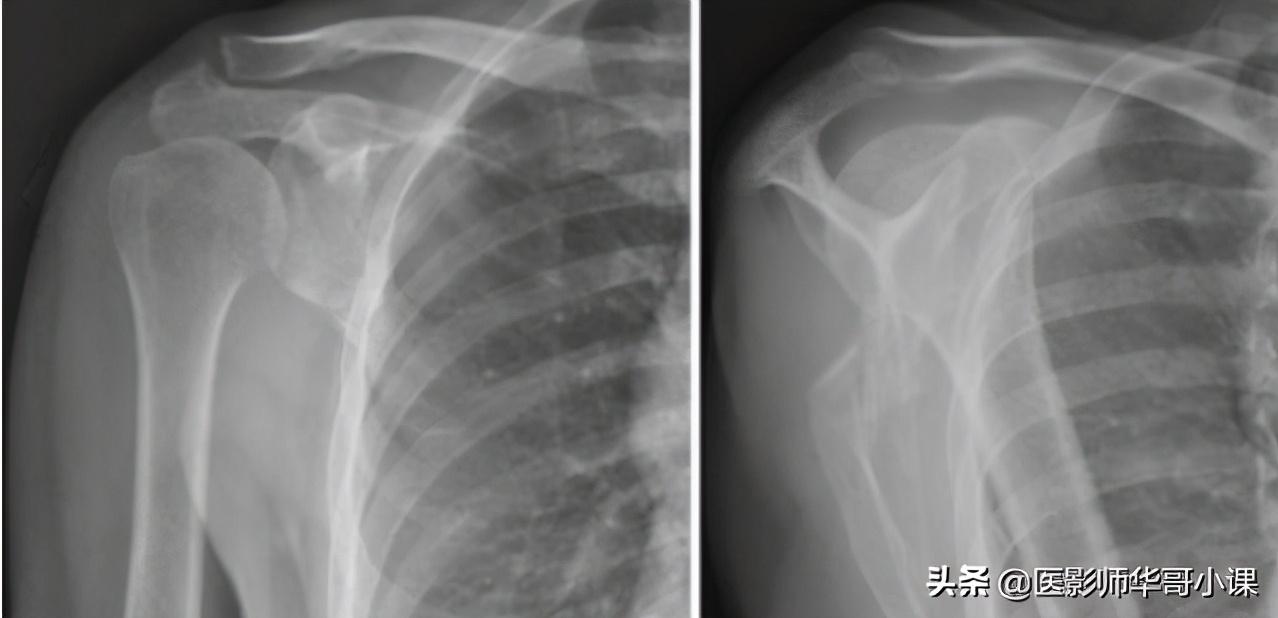

第三节 上臂与肩

1.成人肱骨大结节部皮质较薄,海绵骨较多,因此密度较低,有时很难肯定是正常情形还是早期破坏。

2.婴儿肱骨头的内侧半化骨核先出现,当大结节的化骨核尚未出现时,在正位片上,肱骨头的化骨核偏于一侧,在内旋时化骨核外移,位于肱骨的正中。

3.成人的肱骨结节间沟有时可能很深,在侧位片上好像骨皮质缺损,在轻度旋转使大结节嵴,小结节嵴相错时,又好像皮质增生,新生儿手臂上举用外旋位时,结节间沟影可似骨膜炎。

4.青年人的肱骨近端外侧边缘可见一平行的条状阴影,在有些照片上,还可见到在肱骨外上髁边缘有一平行条状阴影。向骨干边缘伸延8~10cm,此系由于肱骨本身边缘较厚且锐利所造成的,并非骨膜增厚。

5.肱骨头或颈部可能发现环形及圆形致密阴影,此乃软骨岛或骨岛影。

6.髁上突,起于肱骨骨干下1/3前内侧,如钩状突起。

7.肩胛骨下角,肩峰喙突和关节盂的二次化骨核,在16~18岁时钙化,25岁愈合,偶可终生不愈合。

8.肩峰骨,肩峰端在15~16岁时可出现2~3个或更多的骨化中心,首先由各骨化中尽互相融合,然后在20岁时与肩峰融合,在未愈合前有一裂逢,儿童时期裂逢距离较大,如在25岁以后还未与肩峰连接称肩峰骨,此骨可呈三角状,并可与锁骨构成关节,肩峰骨往往对称出现。

9.在肩关节盂的上缘,肩胛骨骨质中,有时可见到密度减低的阴影,这是由于关节盂的底部,部分喙突,部分肩岬骨的骨骼阴影互相交叉重叠对比而成。

10.肩胛骨体部有时可以看到放射状的营养血管沟,不可误认为是骨折线。

11.肩胛骨的上缘有时因为肩胛骨上的横韧带骨化,使上缘与喙突间呈马鞍状畸形,其中有小孔。

12.喙锁韧带处的滑囊可以钙化,多位于喙突及锁骨之间,可有鸡蛋大小。

13.锁骨菱形压迹在锁骨胸骨端下缘往往可以见到一个菱形的骨质凹陷,可以单侧或双侧出现,在胸锁韧带的附着处。

14.锁骨的喙突结节有时可以与肩胛骨的喙突形成关节,为先天变异。锁骨解剖形态为“S”状,投照时如果肩部扭向前方或仰卧位正位投照,锁骨一部分骨干与中心线垂直呈局限性密度增高区,并且锁骨骨干显示缩短,则很象骨折后的重叠。

15.锁骨中孔又名锁骨上孔,位于锁骨中段,有时为双侧性,呈小圆形透明区,X线的发现率为2~6%,骨标本为6.6%。